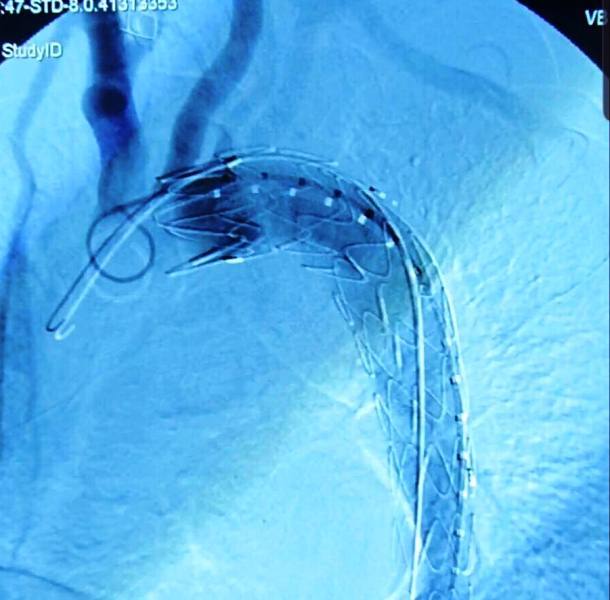

Hình chụp sau khi đặt stent nội mạch ngay đoạn vỡ eo động mạch chủ. Ảnh:BSCC

Ngày sau khi tiếp nhận ê-kíp bệnh viện triển khai can thiệp đặt stent nội mạch ngay đoạn bị vỡ. Sau ca can thiệp, hiện bệnh nhân hồi phục ổn định và được cho xuất viện trong vài ngày tới.

Thông thường bệnh nhân vỡ eo động mạch chủ được chi định phẫu thuật vá chỗ vỡ, tỷ lệ thất bại cao. Hiện, bác sĩ đã làm chủ kỹ thuật can thiệp qua đường ống thông giúp điều chỉnh dòng chảy trong lòng mạch, nên tỉ lệ thành công cao, bệnh nhân có thể xuất viện sớm.